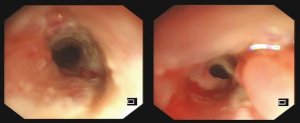

One month later, the patient was readmitted for preoperative evaluation. After neoadjuvant chemotherapy, CT revealed the location of the lesion showed a chemotherapy-induced change. Multiple air spaces were visible at the primary lesion site, and there was no obvious tumor regression (Figure 1). Esophagoscopy suggested chemotherapy-induced changes at 15 to 20 cm from the incisors, and a neoplasm with ulcers was still visible. A rupture was suspected at 20 cm from the incisors, with occasionally emerging bubbles, suggesting a possible esophageal fistula (Figure 2). Tracheoscopy revealed that the mucosa of the tracheal membrane about 5 cm above the tracheal carina was significantly swollen, and the nearby lumen was narrow (Figure 3).